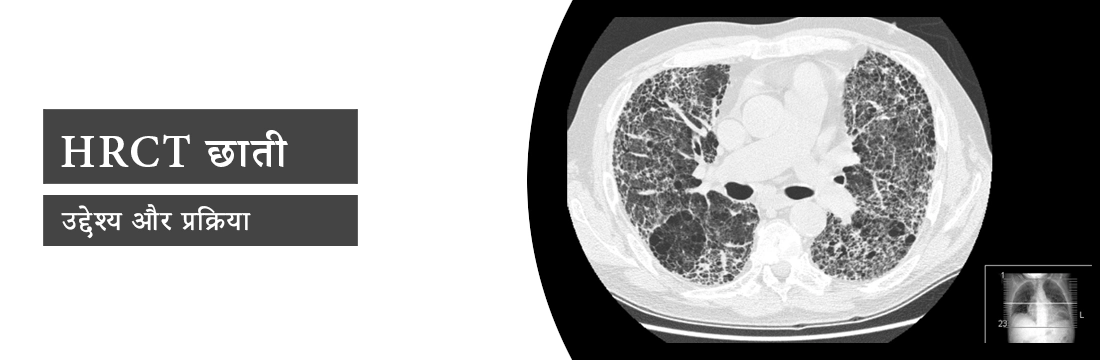

यह लेख HRCT छाती स्कैन, इसके उद्देश्य और प्रक्रिया के बारे में विस्तार से बताएगा।

HRCT छाती क्या है?

HRCT छाती का मतलब है हाई-रिज़ॉल्यूशन कंप्यूटेड टोमोग्राफी, जो उच्च-गुणवत्ता वाली पतली-स्लाइस छाती की छवियों को उच्च-स्थानिक-आवृत्ति पुनर्निर्माण एल्गोरिदम में पोस्ट-प्रोसेस करने के लिए डायग्नोस्टिक टूल है। यह प्रक्रिया बेहतरीन फेफड़ों के विवरण के साथ छवियां बनाती है, जिनका उपयोग डिफ्यूज इंटरस्टिशियल लंग डिजीज का आकलन करने के लिए किया जाता है।

HRCT छाती का उद्देश्य?

HRCT छाती का उद्देश्य फेफड़ों की सबसे छोटी संरचनाओं की जांच करना और बीमारी में सूक्ष्म परिवर्तनों का पता लगाना है। डायग्नोस्टिक विधि निम्नलिखित की जांच करेगी:

- वातस्फीति।

- इंटरस्टिशियल लंग डिजीज।

- सिस्टिक लंग डिजीज।

- छोटी वायुमार्ग की बीमारी।

- पल्मोनरी माइक्रो नोड्यूल।

- ब्रोंकिक्टेसिस।

- लिम्फैंगियोलेयोमायोमैटोसिस (LAM)।

HRCT छाती प्रक्रिया क्या है?

HRCT छाती एक CT स्कैनर में किया जाता है, जो एक डोनट के आकार की मशीन है। मरीजों को बिस्तर पर लिटाया जाता है और बिस्तर स्कैनर में स्लाइड हो जाता है। स्कैनर फेफड़ों की क्रॉस-सेक्शनल इमेज या स्लाइस लेता है। स्कैनिंग के दौरान, तकनीशियन स्पष्ट चित्र प्राप्त करने के लिए साँस लेने या छोड़ने या साँस को रोकने के लिए कह सकता है। स्कैनिंग पूरी होने के बाद, बिस्तर स्कैनर से बाहर निकल जाएगा। HRCT स्कैन कंट्रास्ट का उपयोग किए बिना किया जाता है, इसलिए सुई चुभने और कंट्रास्ट की एलर्जी की कोई चिंता नहीं है।

HRCT छाती एक डायग्नोस्टिक इमेजिंग टूल है जो वातस्फीति, अंतरालीय फेफड़े की बीमारी, सिस्टिक फेफड़े की बीमारी आदि जैसी असामान्यताओं के निदान के लिए फेफड़ों की उच्च कंट्रास्ट डिटेलिंग छवियां प्राप्त करने के लिए एक्स-रे का उपयोग करता है। स्कैनिंग में रोग का पता लगाने के लिए कंट्रास्ट का उपयोग शामिल नहीं है, इसलिए रोगियों के लिए कोई एलर्जी संबंधी समस्या नहीं है।